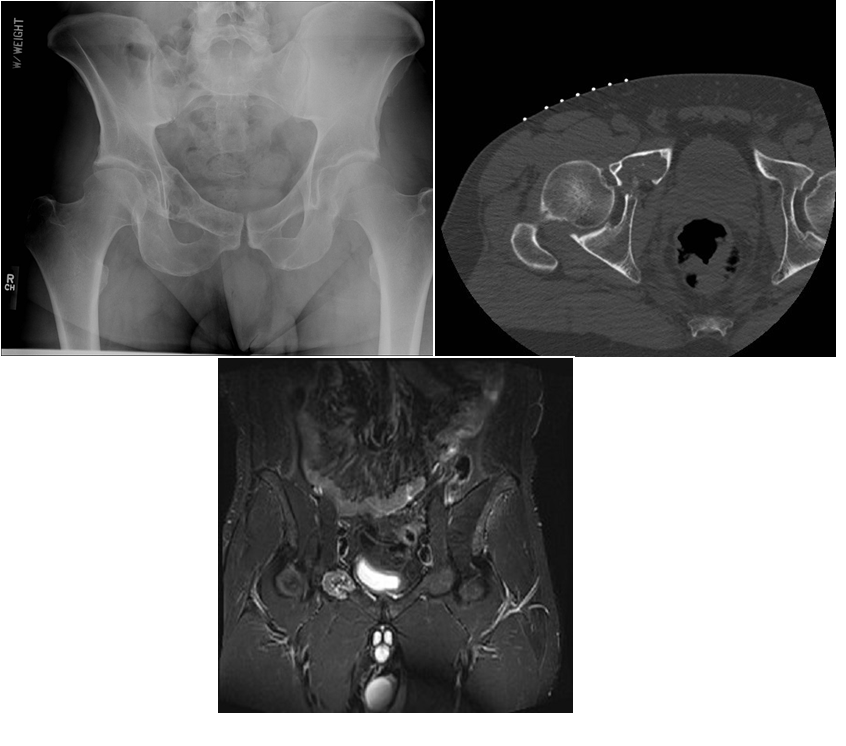

A 79-year old female presents with complaints of right hip pain for 2 months. She denies prior injury or precipitating event. The pain is made worse by lying on the affected side and occasionally hurts with hip motion. The pain is improved with NSAIDS and placing ice on the lateral aspect of her hip. Her primary care physician ordered x-rays which showed a bone lesion in the proximal femur. Her PCP was concerned she had bone cancer and ordered an MRI of the thigh to further evaluate. AP x-ray and a coronal MRI image are shown above. The patient denies a history of weight loss, fatigue, and history of cancer. On exam the patient has no pain with passive range of motion of the hip in all planes. She has pain with palpation over the greater trochanteric bursae. Motor and sensation are intact throughout the lower extremities. What is the most likely cause of this patient’s pain?